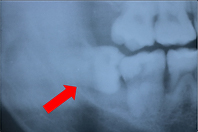

下の写真は、親知らずが横向きに生えていて隙間があります。

下の写真は、その隙間に食べかすが入ってしまっています。

この隙間は下の方が深歯ブラシが届かず、このままでは親知らずと手前の歯が2本とも虫歯になってしまうので抜いたほうが良いケースです。